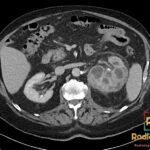

Diagnosis: Appendiceal Mucocele

- CT: Round or tubular low-attenuation (17-26 HU) cystic mass near water density; well-encapsulated; wall calcification is a strong diagnostic feature; wall irregularity and mural nodularity suggest malignancy (cystadenocarcinoma).

- Signs: Onion-Skin Sign: Pathognomonic ultrasound finding of multiple echogenic layers; Whorly/Onion Peel Appearance: CT description of layered mucin within the dilated lumen.

- Wall calcification on CT is highly specific for the diagnosis, though present in less than 50% of cases.